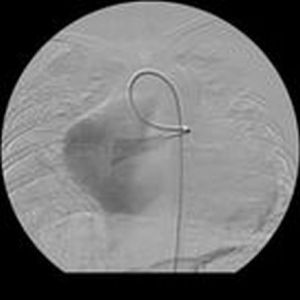

導管置入減影圖2.股動脈穿刺成功後,立即由靜脈內注射肝素50mg,防止血栓併發症。